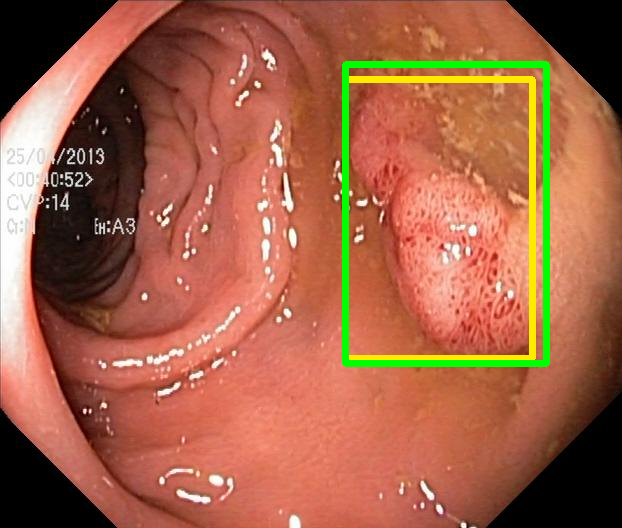

We evaluate the resulting object detection models using the test data, which is pre-processed in the same manner as the validation data, with AP@[.5:.95] (AP for conciseness), AP@.5 (AP5050{}_{50}start_FLOATSUBSCRIPT 50 end_FLOATSUBSCRIPT), and AP@.75 (AP7575{}_{75}start_FLOATSUBSCRIPT 75 end_FLOATSUBSCRIPT) computed for predicted bounded boxes with a confidence score \geq0.05. For all metrics, a higher value indicates better performance. The results are presented in Table VI, and some examples for predicted bounding boxes with a confidence score \geq0.5 are shown in Fig. 1.

RN-HK-MC RN-HK-BT RN-IN-MC RN-IN-BT RN-IN-SL RN-NA-NA Refer to caption Refer to caption Refer to caption Refer to caption Refer to caption Refer to caption Refer to caption Refer to caption Refer to caption Refer to caption Refer to caption Refer to caption VT-HK-MC VT-HK-MA VT-IN-MC VT-IN-MA VT-IN-SL VT-NA-NA Refer to caption Refer to caption Refer to caption Refer to caption Refer to caption Refer to caption Refer to caption Refer to caption Refer to caption Refer to caption Refer to caption Refer to caption

Figure 1: Targets (yellow bounding boxes) and predictions (green bounding boxes) for two randomly selected instances of the Kvasir-SEG test set. For conciseness, we denote ResNet50s with RN, ViT-Bs with VT, Hyperkvasir-unlabelled with HK, ImageNet-1k with IN, MoCo v3 with MC, Barlow Twins with BT, MAE with MA, supervised pretraining with SL, and no pretraining with NA-NA.